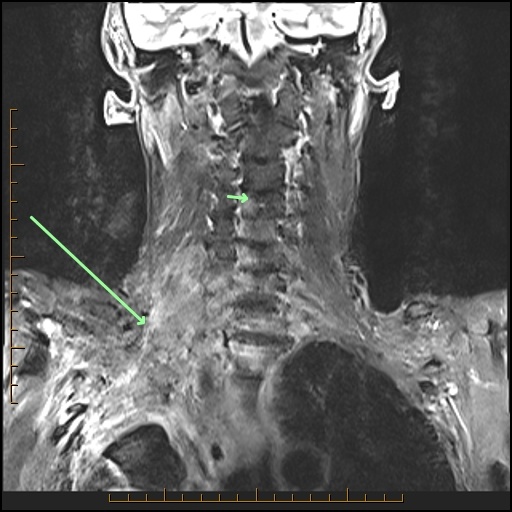

The arrows point to what primary tumor in this 77-year-old male with lung cancer? What’s invaded? Is it cleanly resectable? Come up with your own answers, then check below the images to see my findings.

A Pancoast tumor (arrow) which crosses the cupola (fat pad at lung apex) of the lung, invades the brachial plexus and the vertebra. It is NOT resectable.

ProScan Pearl: Check the lung apex on every cervical spine MRI.